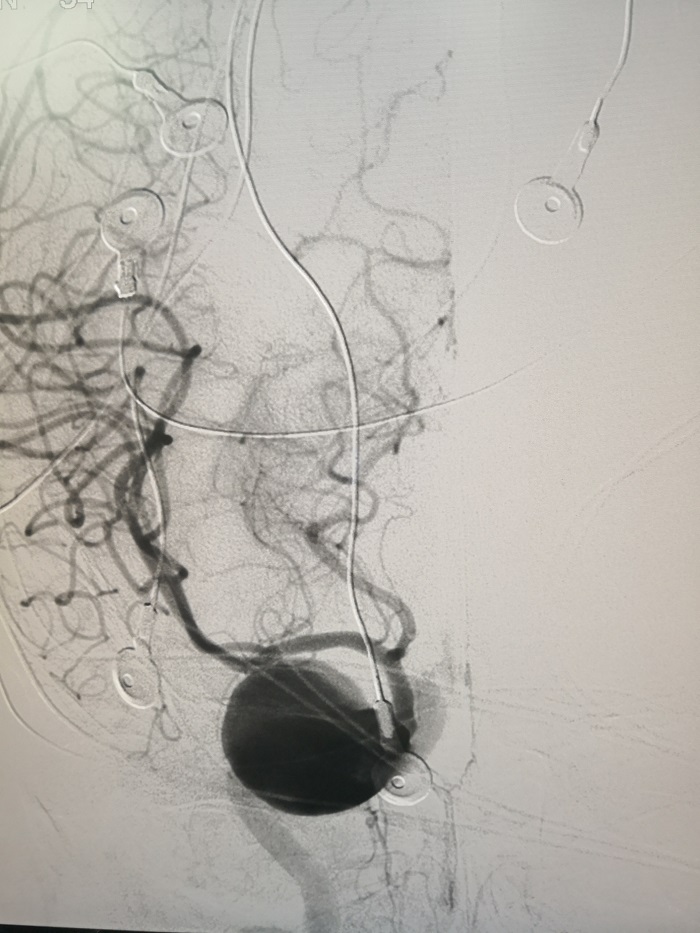

近日,我院神經(jīng)外科收治了一名62歲的女性患者。該患者因右側(cè)顳部頭痛及右眼內(nèi)聚,行全腦血管造影術(shù)檢查發(fā)現(xiàn)顱內(nèi)巨大動(dòng)脈瘤,直徑達(dá)3cm,接近乒乓球大小,且出現(xiàn)即將破裂跡象!

直徑達(dá)3cm的顱內(nèi)巨大動(dòng)脈瘤

7月22日上午,神經(jīng)外科腦血管介入專家陳建民醫(yī)生團(tuán)隊(duì)聯(lián)合神經(jīng)內(nèi)科電生理專家侯蘊(yùn)琦醫(yī)生團(tuán)隊(duì),為患者實(shí)施了腦電監(jiān)測(cè)下右側(cè)頸內(nèi)動(dòng)脈球囊閉塞試驗(yàn)。結(jié)果顯示,右側(cè)頸內(nèi)動(dòng)脈近端閉塞45分鐘,患者無不適,左側(cè)肢體活動(dòng)正常,腦電活動(dòng)完全正常。根據(jù)試驗(yàn)結(jié)果,神經(jīng)外科團(tuán)隊(duì)于當(dāng)天下午順利為患者實(shí)施動(dòng)脈瘤部分栓塞及載瘤動(dòng)脈近端閉塞術(shù)。術(shù)后,患者頭痛癥狀得到大部分緩解,視力無下降,四肢活動(dòng)好,術(shù)后3天就步行出院。患者及家屬對(duì)我院的團(tuán)隊(duì)合作及治療效果表示非常贊賞和滿意。